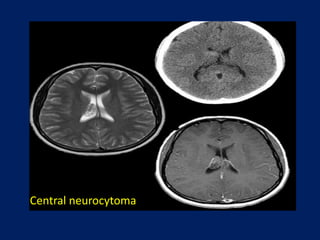

Central neurocytoma